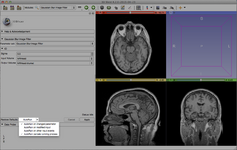

Slicer is a community platform created for the purpose of subject specific image analysis and visualization.

- Multi-modality imaging including, MRI, CT, US, nuclear medicine, and microscopy

- Multi organ from head to toe

The Markups module replaces Annotation fiducials.